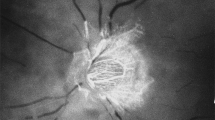

1. In my FFA studies on central retinal artery occlusion in the early 1960s, I noticed that the optic nerve head (ONH) showed vascular filling but no filling of the retinal vasculature (Fig. 1); [2, 3] this finding contradicted the then prevalent concept that the ONH was supplied by the central retinal artery. Thus, this new finding showed for the first time that the ONH was supplied by the PCA circulation and not by the central retinal artery. And FFA also unveiled the in vivo filling pattern of the choroid.

Fundus photograph (a) and fluorescein fundus angiogram (b), of left eye of a GCA patient with arteritic AION, and a cilioretinal artery occlusion. a Fundus photograph shows a classical appearance of arteritic AION, i.e., chalky white optic disc oedema with some hyperaemia. b Fluorescein fundus angiogram shows normal filling of the area supplied by the lateral PCA, but no filling of the area supplied by the medial PCA (including the entire optic disc, with no perception of light).